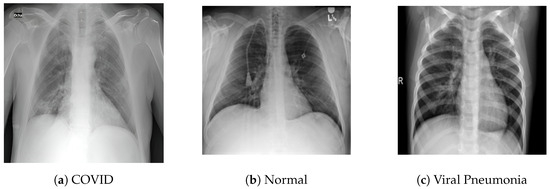

3.1.1. COVID-19 Radiography Database